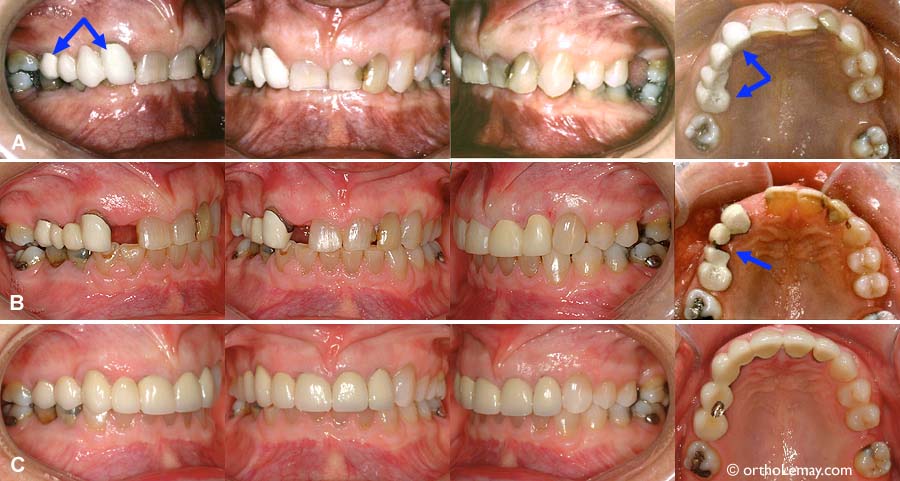

(A) Absence des 2 latérales supérieures. L’espace s’est fermé à droite et il y a un pont du côté gauche (flèche bleue). Une incisive inférieure a été extraite pour aligner les dents du bas (flèche jaune).

(B) Fin de l’orthodontie; l’espace pour la latérale supérieure droite a été ouvert et une dent temporaire a été collée sur une attelle de rétention (flèche jaune). Le pont gauche a été modifié mais est toujours en place. Une greffe de gencive a été faite pour couvrir les racines des incisives inférieures qui se sont déchaussées (flèche bleue). Des espaces sont présent entre les incisives inférieures près de la gencive.

(C) Un implant et une couronne remplacent chaque latérale (flèches jaunes), une couronne a été faite sur la canine supérieure gauche, les espaces inter-dentaires ont été comblés par le dentiste avec du composite (flèches bleues).